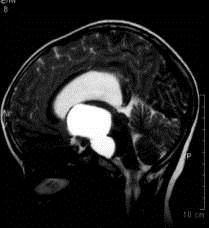

问题 病历摘要:??患者女性,6岁,半年来感觉视力模糊,近10天出现反复头痛,间有恶心呕吐,精神转差,查体:神志清楚,身高90cm,体重25Kg,血压90/55mmHg,右眼视力4.6,左眼视力4.8,双侧视乳头水肿,颈软,伸舌居中,四肢肌张力正常,肌力5级,双侧Babinski征(-)。 患者术后第一天,神志嗜睡,精神疲倦,皮肤干燥,38.2℃,心率155次/分,Bp102/60mmHg,中心静脉压3mmHO,Na160mmol/L,尿量很多,色清如水,应作的处理措施有?